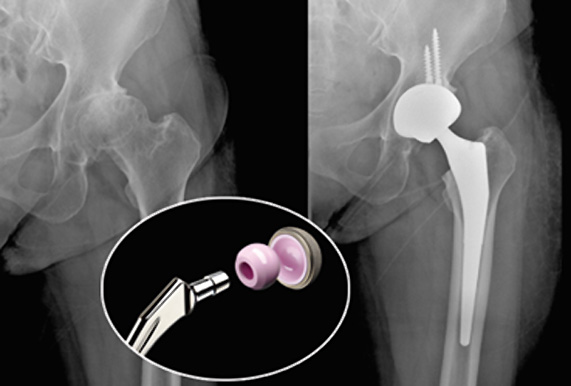

퇴행성 관절염, 무혈성 괴사등으로 심하게 손상된 고관절을 인공 관절로 교체하는 수술입니다.

퇴행성 관절염이나 무혈성 괴사 등으로 인해 고관절에 심한 통증이 지속될 때

절뚝거리거나 다리를 절고 걸을 때

낙상으로 인한 고관절 부위 골절일때